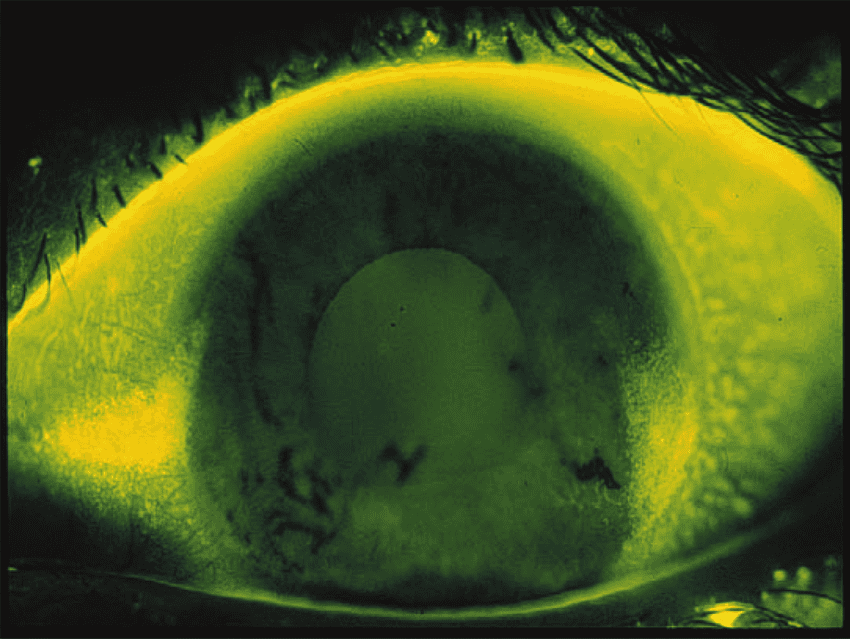

Dry Spots

Areas of drying as noted by absent areas of fluorescein-stained tear film on the cornea when the patient stares.